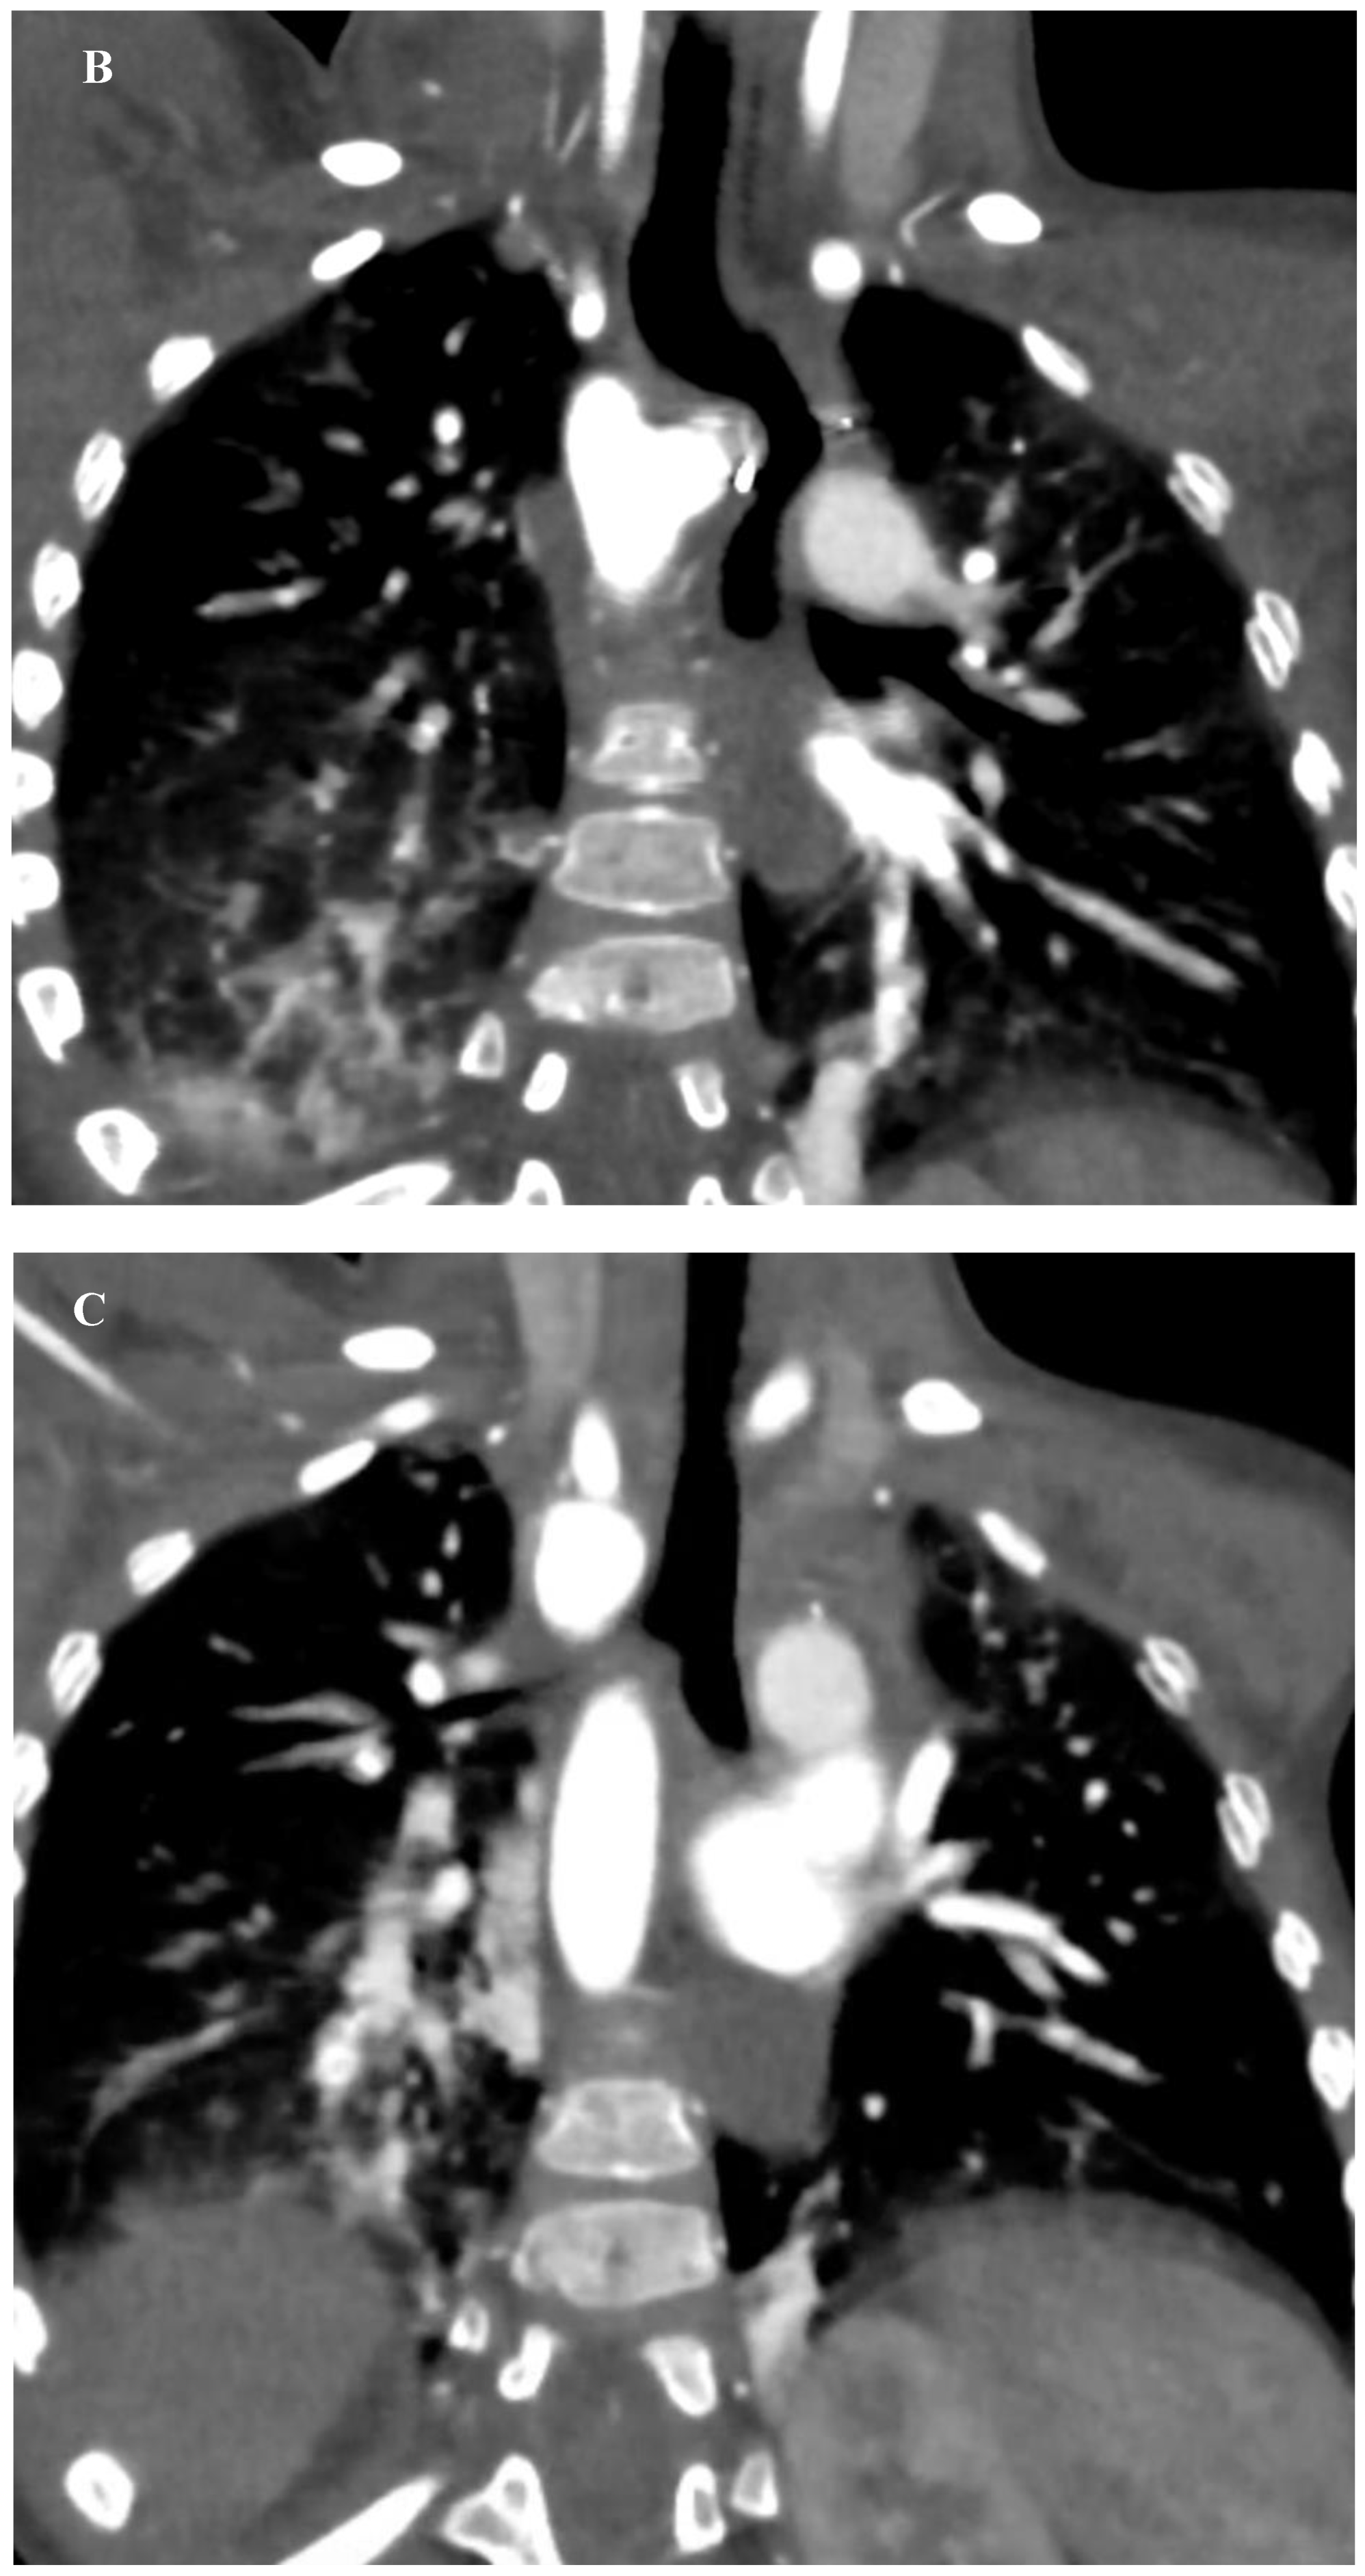

The patient was then placed on a gastrostomy tube and followed up until 14 months of age, showing persistent dysphagia and weighing 8.2 kg. Hence, the decision was made to perform a surgical repair of the vascular ring. Prior to the surgical incision, an endoscopic and EndoFLIPTM evaluation were conducted, demonstrating an esophageal narrowing at the level of the vascular ring and an abnormal increase in esophageal impedance, respectively. Subsequently, a limited left posterior thoracotomy was performed, allowing the visualization of a left-sided esophagus with a RAA originating from behind, and an aberrant LSA exiting from a KD. The LLA, observed compressing the esophagus, was divided. The KD was obliterated with two purse-string sutures, and the aberrant LSA was dissected and divided from the aorta, then re-implanted into the left carotid artery (LCA) via an end-to-side anastomosis. Following closure of the chest, another endoscopic and EndoFLIPTM evaluation were performed which evidenced an improvement in esophageal narrowing and impedance, respectively. The patient’s recovery was uneventful, and she was discharged on postoperative day 4. During the follow-up visits, she was asymptomatic and meeting her growth milestones. A recent CTA performed 2 years post- procedure revealed a patent re-implanted LSA into the LCA and no tracheal deformities (Figure 3) (Supplementary material 2, 3, and 4).

Figure 3. Postoperative Computed Tomography Angiography. (A) 3D reconstruction showing a RAA status post KD plication and LSA transposition into the LCA, evidencing patency of the re-implanted artery and an outpouching of the KD’s remnant with a surgical clip in the distal end. (B) coronal view demonstrating esophageal displacement without evident narrowing. (C) coronal view evidencing no tracheal deformities.